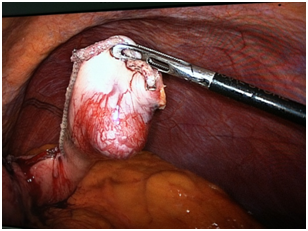

Under general anesthesia a laparoscopic exploration was performed. A 3cm tumor was found at the posterior wall of the stomach (Figure 2). There were no other pathological findings during the exploration of the abdomen cavity. A wedge resection of the tumor was performed using laparoscopic staplers. The patient had uneventful recovering period and was discharged 5days after surgery. On slides taken from lesion showed the round cells with small uniform nuclei, without nuclear pleomorphic and no mitotic figures. The distribution of round glomus cells around the open vascular lumen is a key to the pathology diagnosis. The lesion was positive for alpha-smooth muscle Actine (alpha SMA), Calponin and negative for CD-34, C-KIT and CK MNF116. The proliferating marker showed very low mitotic rate, less than one per 50 HPF. The histological examination and immunohistochemical stains confirmed diagnosis of gastric glomus tumor (Figure 3). The surgical resection margins were free of tumor.

Figure 2 A 3cm tumor was found at the posterior wall of the stomach.